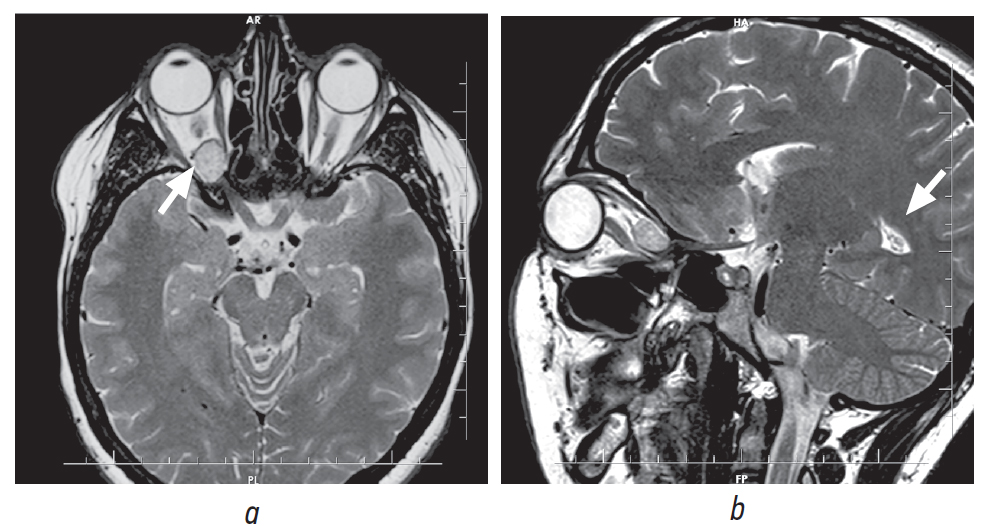

На основании данных нейровизуализационных методов исследования было выделено две группы пациентов: группа 1 — 29 пациентов c КВМ орбиты, распространяющейся в полость черепа, из них 15 с распространением в ВГЩ и ЗК, 8 пациентов — в ВГЩ, 2 — в ЗК, 3 — в ВГЩ и нижнюю глазничную щель, у 1 пациента КВМ орбиты распространялась в полость черепа с разрушением крыши орбиты; в группу 2 включены пациенты с КВМ, локализующейся только в орбите, — 21 пациент (рис. 2, 3).

Рис. 2. Магнитно-резонансная томография. Кавернозная венозная мальформация орбиты, распространяющаяся в полость черепа через верхнюю глазничную щель и зрительный канал: а — аксиальная проекция, режим Т2; b — сагиттальная проекция, режим Т2

Fig. 2. Magnetic resonance tomography. Cavernous venous malformation of the orbit, spread into the cranial cavity through the superior orbital fissure and the optic canal: а — axial projection, T2 mode; b — sagittal projection, T2 mode